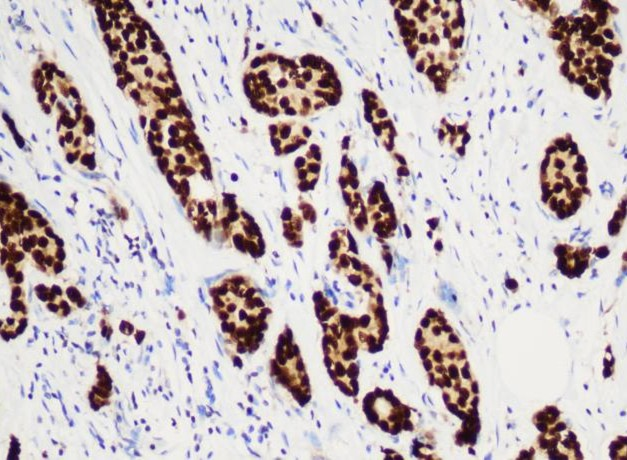

达科为提供200+种IHC一抗产品,有鼠源和兔源两类抗体,手工和仪器均可适配,一抗产品均为单克隆抗体,能够确保与目标抗原结合的特异性,同时一抗具有极高的灵敏度,可以在样本中检测到低表达水平的目标抗原,并获取可靠的结果。